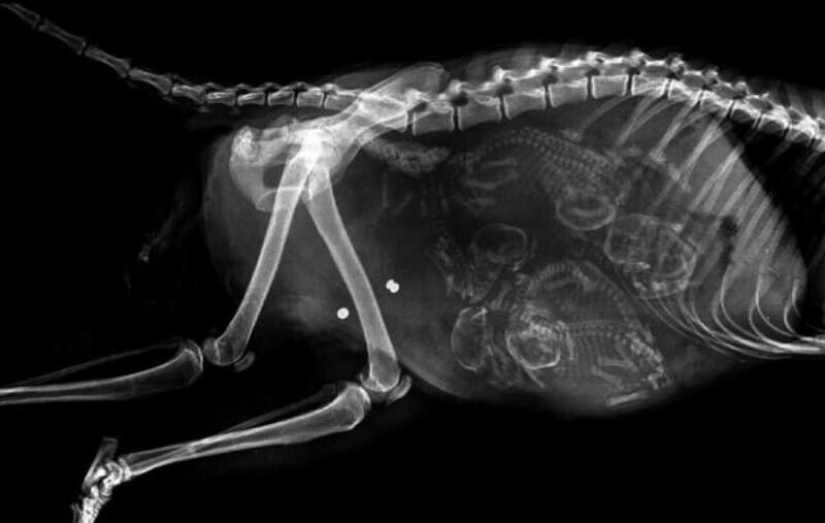

tortuga preñada